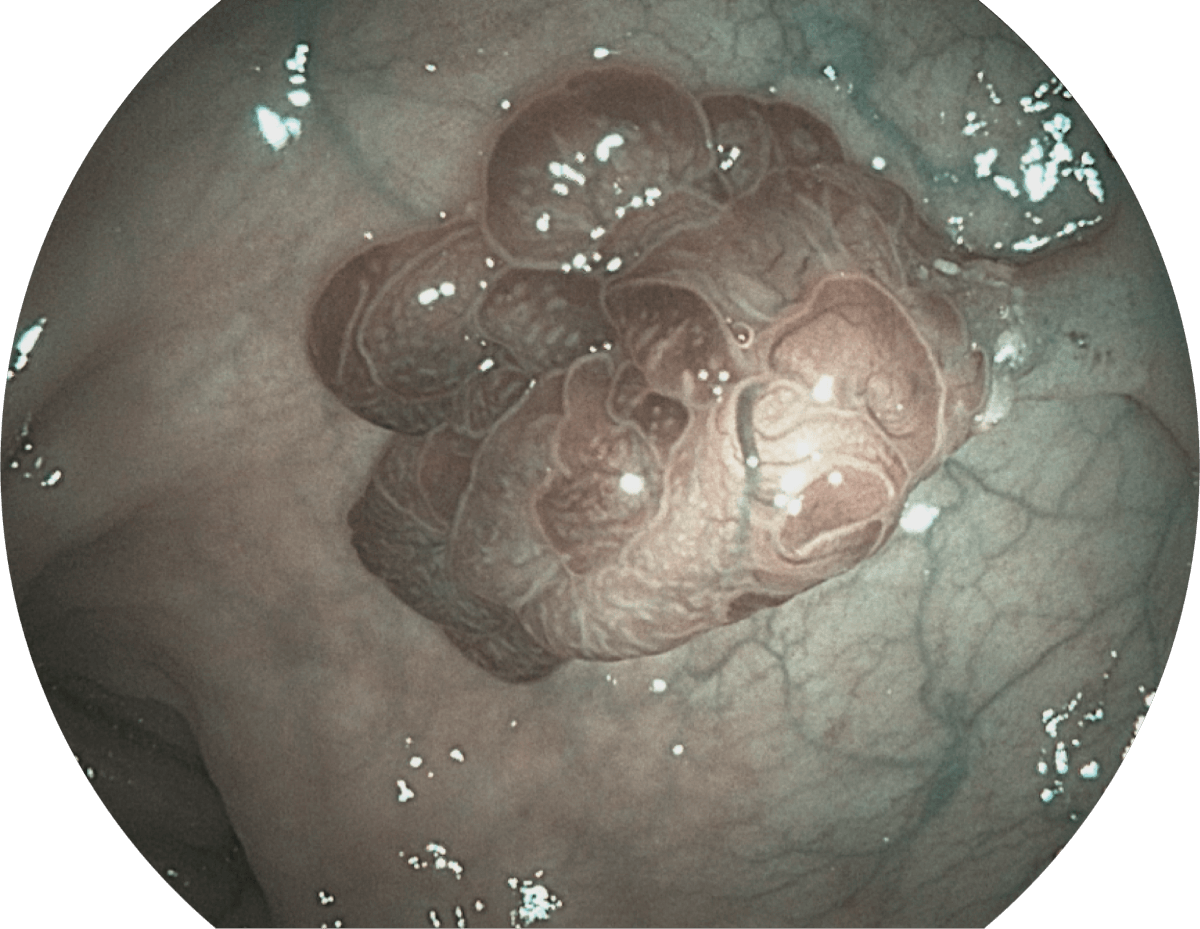

强调浅层黏膜结构的同时,保证照明亮度和提升浅层微血管与中层血管颜色对比度,病变边界更清晰。

• VIST